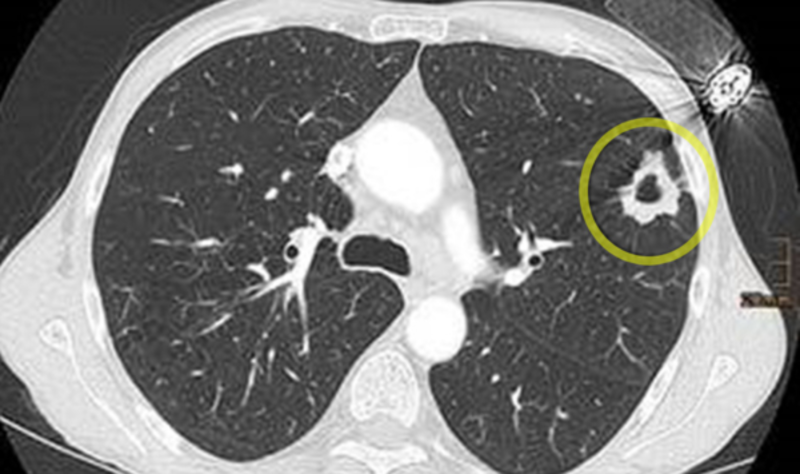

Das Universitätsklinikum Freiburg hat als erste Klinik in Baden-Württemberg die Genehmigung erhalten, Lungenkrebsscreening für starke Raucher*innen in der klinischen Versorgung anzubieten. Mit einem Computertomogramm (CT) können selbst kleinste Veränderungen früh erkannt werden – lange bevor Beschwerden auftreten. Durch die eingesetzte Niedrigdosis-Technik und die modernsten CT-Scanner ist die Untersuchung besonders schonend. Das Programm eröffnet Betroffenen eine bessere Chance auf Heilung und stärkt die onkologische Versorgung im Land nachhaltig.

Computertomogramm der Lunge. Die Zigaretten und das Feuerzeug stecken noch in der Brusttasche. Der Tumor wächst direkt darunter in der Lunge. ©Universitätsklinikum Freiburg